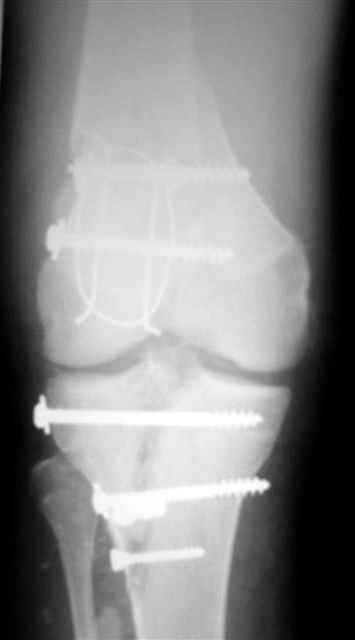

№4 снимок через два дня после операции, супракондилярный перелом, при поступлении конечность была холодная и без пульса, подозрение на повреждение сосудов, сделана ABI (ankle-brachial index) в приемном отделении, индекс меньше 1 к 0.9 в норме 1 к 1.1, срочная ангиография в операционной после Ex-Fix, по два стержня в сегменте наложен в течение 20 мин, повреждение подколенной артерии, ушивание сосудистым хирургом через медиальный доступ в дистальном отделе бедра и двухразрезная профилактическая фацсиотомия, перкутанная фиксация каннюлированными шурупами несмещенного перелома шейки бедра и дополнительные стержни в фиксаторе для жесткости.